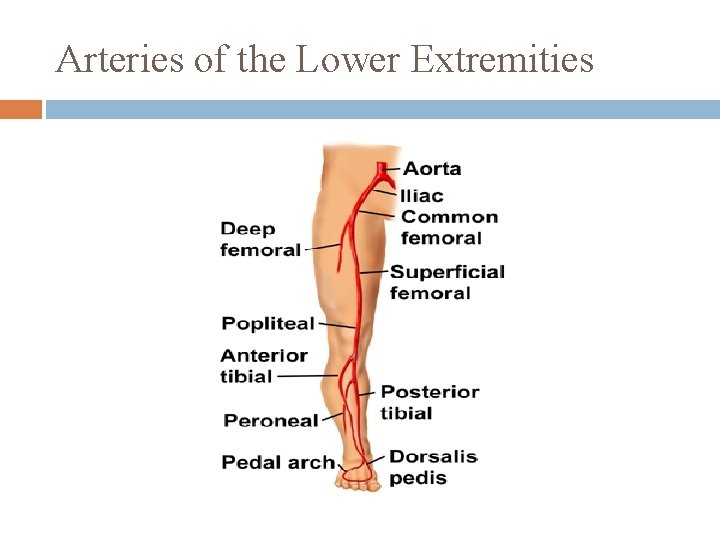

External Iliac Arteries when cross over to medial surface of thigh become Femoral Arteries � branches to deep femoral & superficial femoral when reaches knee becomes Popliteal Artery where it branches posterior & anterior Tibial arteries Posterior Tibial Artery divides Medial & Plantar Arteries

Arteries of the Lower Extremities